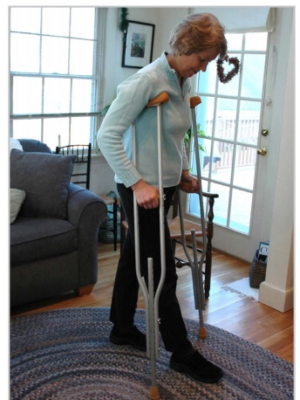

Các cân nhắc về chịu trọng lượng

Sau phẫu thuật có xi măng, thường bệnh nhân được cho phép chịu trọng lượng càng nhiều nếu chịu được ngay sau phẫu thuật. ngược lại trọng phẫu thuật không xi măng hoặc lai, cần hạn chế chịu trọng lượng lên chi mổ vài tuần đầu cho đến 3 tháng.